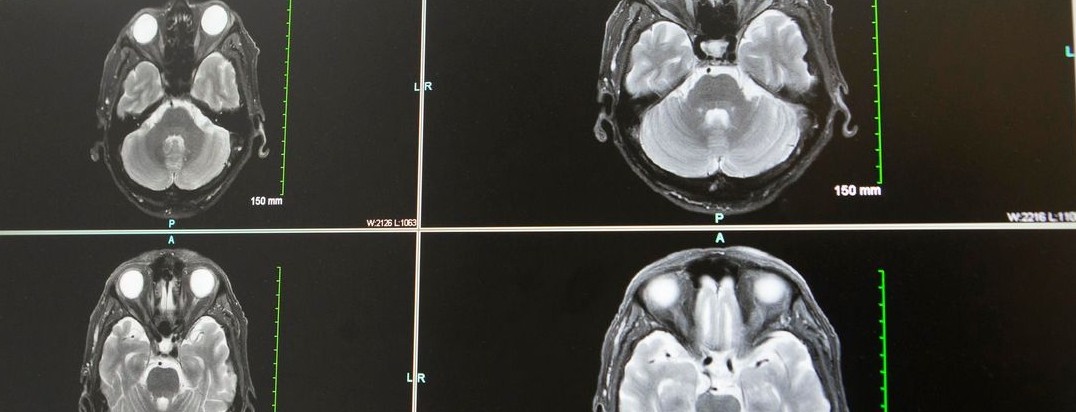

Featured photo at top of brain scans. Photo provided by Joseph Broderick.